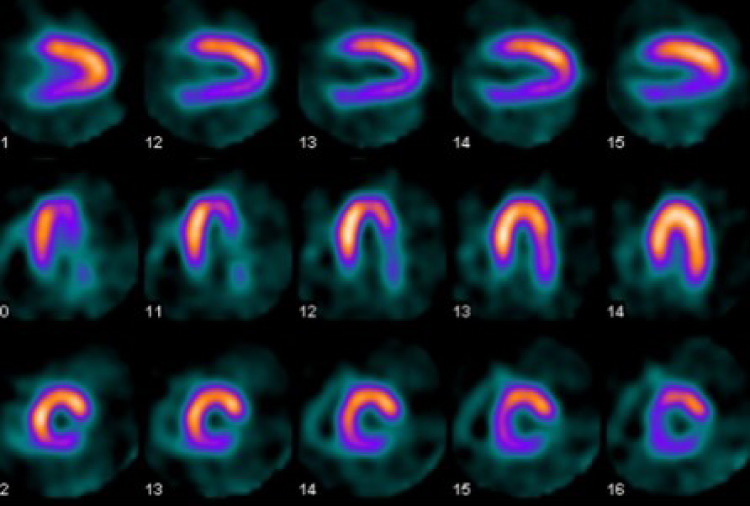

心血管造影・治療

カテーテルを用いて冠動脈造影を行い、どの血管がどの程度細くなっているか、またどの血管が詰まっているのかを調べます。その他、カテーテルを心臓までもっていき、心臓の働きや病気の種類・重症度を詳しく調べることもできます。

狭くなった血管に対しては、先端にバルーン(風船)やステント(金属を網の目状にした筒)を取り付けたカテーテルでバルーンを内側から膨らませて血管を押し広げる治療を行います。

異常な回路や異常な部分に対しては、カテーテルを用いて焼灼または冷凍凝固を行い、不整脈を抑える治療を行います。

主な手技

冠動脈造影(CAG)・経皮的冠動脈インターベンション(PCI)・ローターブレーター・方向性冠動脈粥腫切除術(DCA)・アブレーション